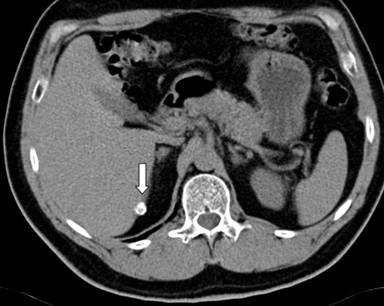

Further etiological investigations were performed, including an abdominal CT which showed a solid mass of 40 mm of diameter with small parietal eccentric calcification located in the body-tail of the pancreas (Figure 1a), encompassing the splenic artery (Figure 1b). Lymph nodes along the small gastric curve, in the inter-aortic and left para-aortic cable, and a calcified lymph node in the lower edge of the liver were also present (Figure 2). No alterations of the other parenchymal organs were detected. A suspicion of pancreatic cancer was pose, although the CA 19-9 was negative (1.6 U/mL; reference range: 0-37 U/mL).

Figure 2. Calcified lymph node in the lower edge of the liver. |